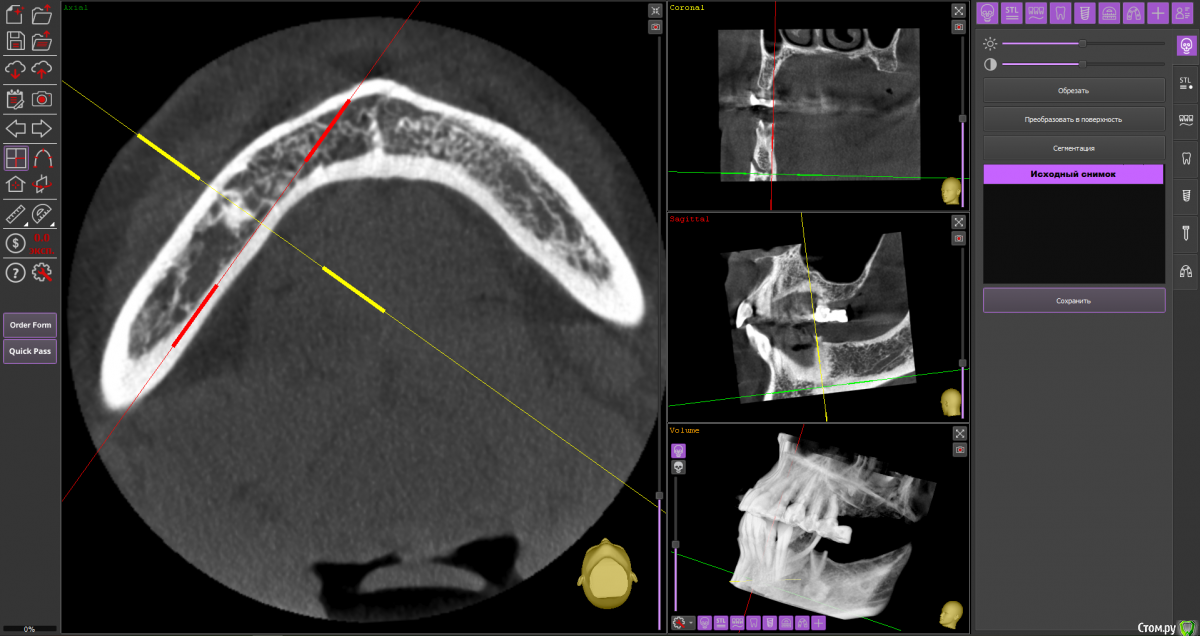

Fin Опубликовано 6 мая, 2020 Поделиться Опубликовано 6 мая, 2020 Здравствуйте коллеги. Пришла пациентка, для установки импланта в обл 3.6. После осмотра КТ обнаружил образование в проекции будущего импланта. В ходе осмотра КТ так же обнаружилось несколько подобных образований по НЧ. Помогите советом, кто сталкивался с подобной ситуацией и что это может быть? Ссылка на комментарий

Дмитрий Л. Опубликовано 6 мая, 2020 Поделиться Опубликовано 6 мая, 2020 Ну сделайте трепан биопсию. Через пару недель можно будет и имплант вкрутить. Я думаю что это костный рисунок. Ссылка на комментарий

wladdX Опубликовано 6 мая, 2020 Поделиться Опубликовано 6 мая, 2020 (изменено) Мне тоже кажется, что вы принимаете балочную структуру и петли н\ч канала за н\образование. Такое встречается иногда. Похожий случай На ОПТГ выглядит уже не так трагично Изменено 6 мая, 2020 пользователем wladdX 1 Ссылка на комментарий

It'sGeorgy Опубликовано 6 мая, 2020 Поделиться Опубликовано 6 мая, 2020 Тоже часто сталкиваюсь с таким. Костный рисунок. 1 Ссылка на комментарий

Fin Опубликовано 7 мая, 2020 Автор Поделиться Опубликовано 7 мая, 2020 Мне тоже кажется, что вы принимаете балочную структуру и петли н\ч канала за н\образование. Такое встречается иногда. Похожий случай46_1.jpg На ОПТГ выглядит уже не так трагичноОПТГ фрагмент.jpgЧестно говоря тоже думаю, что костный рисунок но смутили размеры и то что в других местах кроме этих таких явлений не наблюдается. Сейчас пациент предоставил снимок до ортод. лечения. На нем немного видно костный рисунок. Ссылка на комментарий

Fin Опубликовано 7 мая, 2020 Автор Поделиться Опубликовано 7 мая, 2020 Тоже часто сталкиваюсь с таким. Костный рисунок.Извините, хотел нажать кнопку ответа а поставил минус((.Такое тоже вижу очень часто, но смущают размеры. Ссылка на комментарий